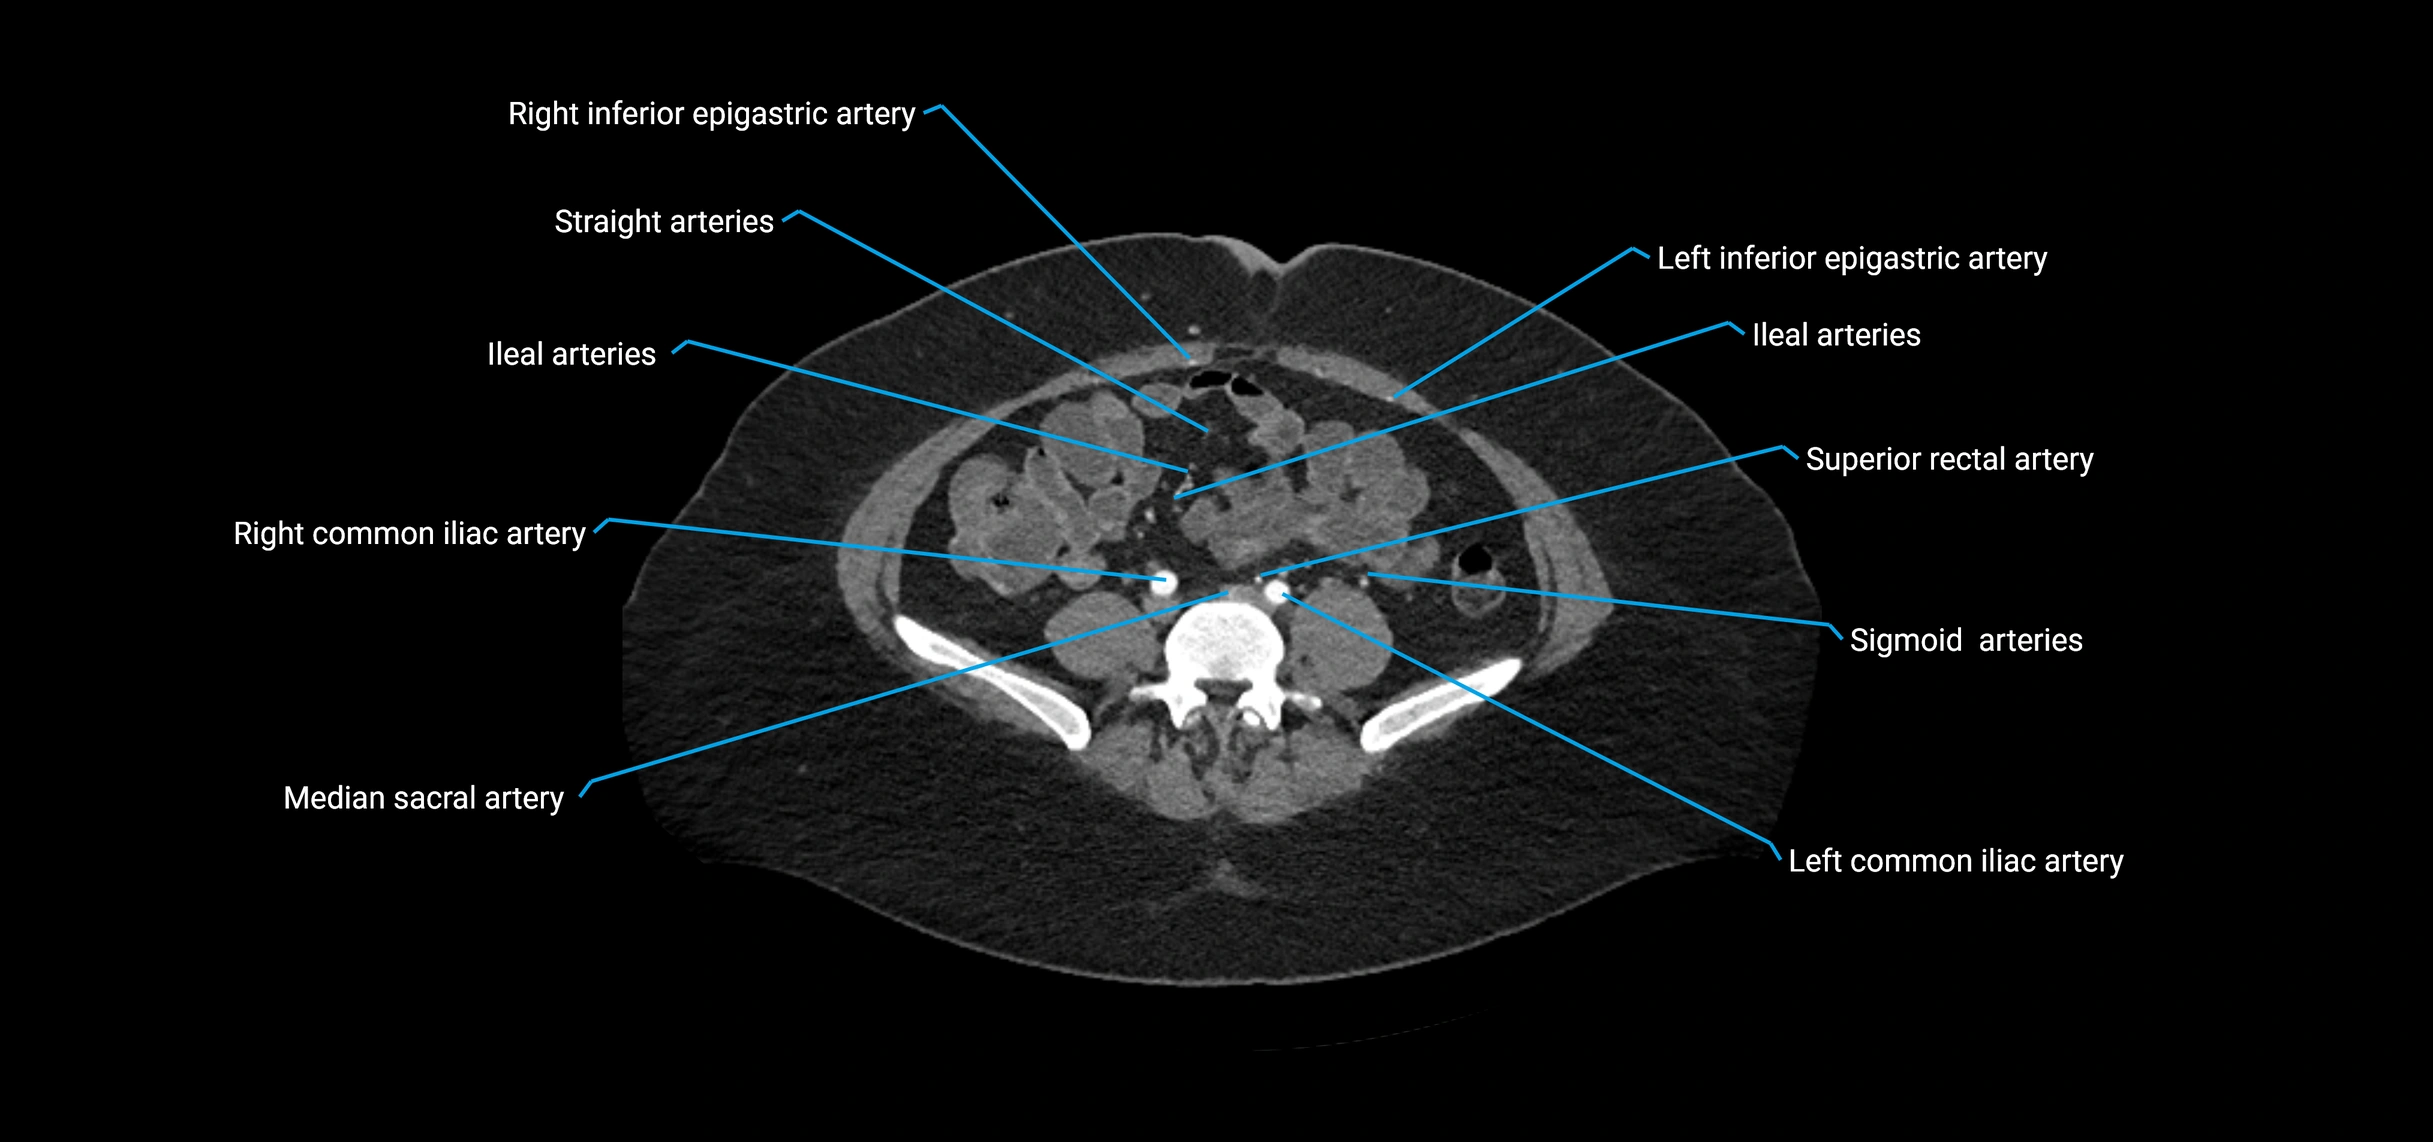

CT Appearance

Non-contrast CT:

• Appears as a tubular soft tissue structure anterior to vertebral bodies

• Calcified atherosclerotic plaques appear as hyperdense foci along the wall

• Useful for screening abdominal aortic aneurysm (AAA) size and mural calcification

Contrast-enhanced CT (CTA):

• Gold standard for abdominal aortic imaging

• Provides excellent detail of lumen, wall, aneurysm, thrombus, and branch vessels

• Multiplanar and 3D reconstructions help in aneurysm measurement, stent graft planning, and dissection evaluation

• Detects acute rupture, traumatic injury, or occlusion with high sensitivity

CT images

image